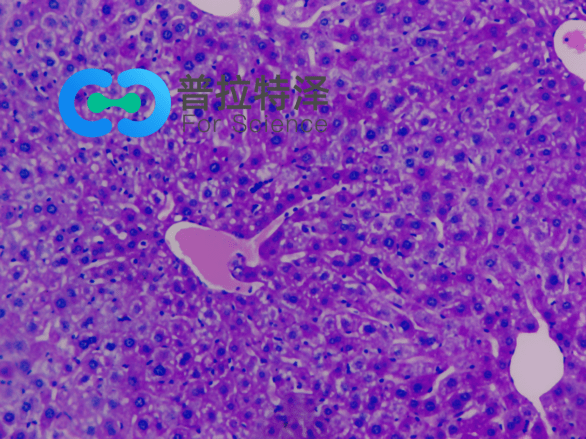

在生物學(xué)和醫(yī)學(xué)領(lǐng)域,PAS染色(Periodic Acid-Schiff Stain)是一種常用的組織染色技術(shù),用于檢測(cè)組織中的多糖類物質(zhì),如糖原和粘多糖。掌握PAS染色的正確步驟,對(duì)于科研人員和醫(yī)學(xué)工作者來(lái)說(shuō)至關(guān)重要。普拉特澤生物——組織染色實(shí)驗(yàn)平臺(tái)操作各類組織的染色實(shí)驗(yàn)上百例,專業(yè)代做PAS染色和各種染色實(shí)驗(yàn),本文將從入門到精通,全面介紹PAS染色的步驟和注意事項(xiàng)。

→Schiff試劑染色:將氧化后的切片放入Schiff試劑中,醛基與Schiff試劑中的亞甲基藍(lán)發(fā)生反應(yīng),形成紫紅色產(chǎn)物。

→蘇木精復(fù)染:用蘇木精對(duì)切片進(jìn)行復(fù)染,使細(xì)胞核呈現(xiàn)藍(lán)色。